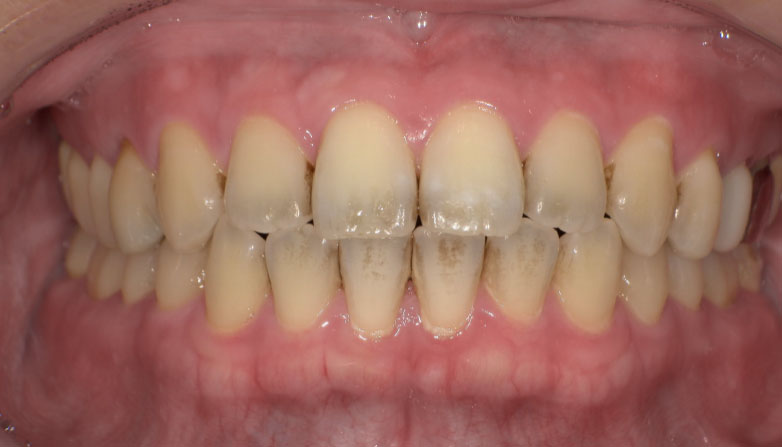

症例1

before

after

| 主 訴 | 着色が気になる |

| 治療期間 | 通院 1回 |

| 治 療 費 | 1回 7,700〜11,000円(税込) |

| 治療内容 | PMTC |

| 治療のリスク | 歯自体の色を白くすることはできない。 歯と歯の間や強い着色などは落とすことが出来ないことがある。 しばらくすると再び着色することがある。 |